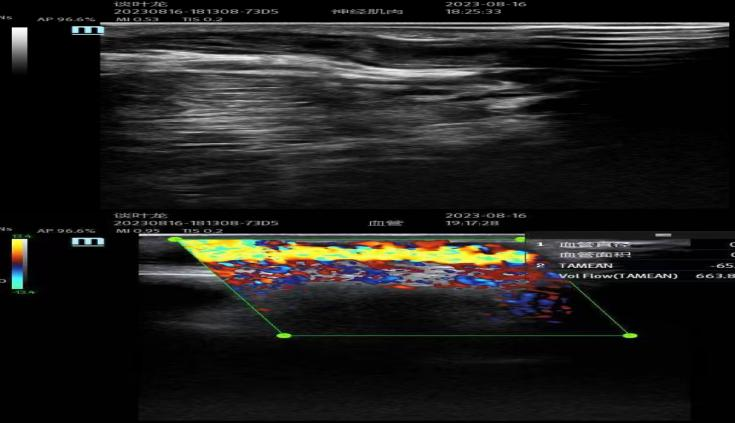

很快病人到达我院,我院肾病学科宋燕飞、李林两位主治医师认真仔细查看病人情况,考虑为血栓导致内瘘血管闭塞,急需重新开通闭塞血管,立即完善相关术前准备,在大家的共同努力下,患者动静脉内瘘血管再通,B超下动静脉血管流量良好。

对于血液透析患者而言,血管通路是患者的“生命线”,目前使用最多的是自体动静脉内瘘,长期的血液透析,反复穿刺,自体动静脉内瘘很容易出现血栓形成、内膜增生、狭窄等情况,使透析不充分、肢体肿胀,甚至无法透析的情况,给患者造成极大困扰,严重影响患者的生存和生活质量。近年来在B超引导下内瘘血管球囊扩张术(PTA)已逐渐取代传统的治疗方法,具有创伤小、疗效好、恢复快、有效保护有限血管资源、内瘘可即刻穿刺无需临时置管进行过渡的特点,己被临床广泛进行应用,PTA手术的开展,填补了我院此项技术空白,为动静脉内瘘血液透析患者带来了福音。